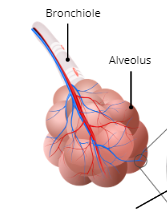

Bronchi

larger airways in the lungs that are supported by cartilage rings

Bronchioles

narrow airways in the lungs (less than 1mm in diameter) that do not contain cartilage rings and connect bronchi to alveoli

Alveoli

small sacs of air

Surfectant

reduces surface tension of fluid in the wet surfaces of the alveoli; are produced by pneumocytes